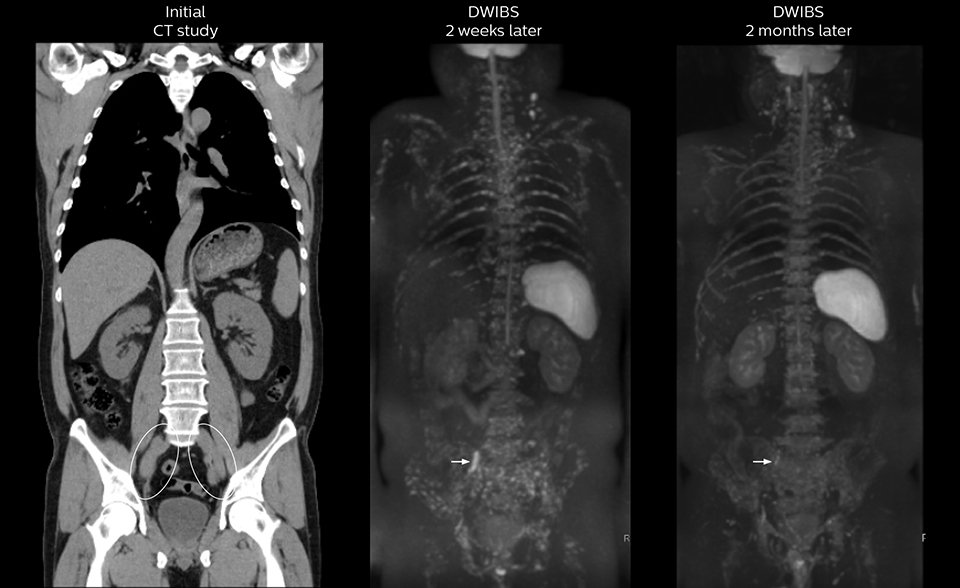

“The DWIBS sequence’s value in oncology cases is due to the high contrast it creates between lesions and surrounding tissue. Whole body DWI is requested by physicians who need to clarify TNM staging or determine therapeutic strategies, oncologists in need of diagnosis or follow-up scans, surgeons who need to see the presence of distant lesions that are sometimes difficult to detect by CT before surgery, and urologists for the evaluation of bone lesions, and the effect of chemotherapy and radiotherapy.”

“mDIXON FFE allows us to quickly get information we need to assess the presence of fat. That gives us more information when we need to diagnose bone lesions, and when we are asked to judge fat-containing lesions such as hepatocellular or renal carcinoma,” Dr. Nobusawa says. “The mDIXON fat images can help us to differentiate fatty bone marrow from bone lesions. This is especially useful in elderly people, who tend to have fattier bone marrow. The water images provide a high signal-to-noise ratio in the intestinal canal, which is valuable for visualizing lesions in the colon,” he says.

Kawasaki Sawai Hospital’s whole body protocol also includes an mDIXON FFE sequence. Because mDIXON provides images for four contrast types – water only, fat only, in-phase and out-of-phase – from a single acquisition, it is useful in many ways.

“In-phase and out-phase sagittal T1-weighted FFE images help us to visualize and further characterize bone lesions such as metastasis and bone-marrow hyperplasia that have high signal on DWI. These images are also used throughout radiotherapy, to monitor changes in the fatty bone marrow.”